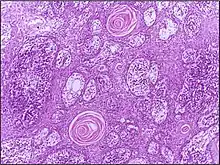

![]() | Squamous cell carcinoma of the skin | Well-differentiated squamous cell carcinoma skin showing malignant cells with mild atypia resembling normal squamous epithelial cells with intercellular bridges, individual cell keratinisation and nests of keratin pearls. | Category: Histopathology of squamous cell carcinoma of the skin | Squamous cell carcinoma |